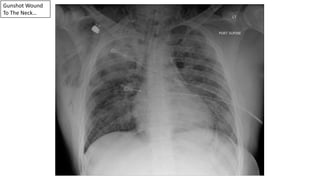

Gunshot Wound

To The Neck…

Injury To The Trachea & Esophagus

Pneumomediastinum